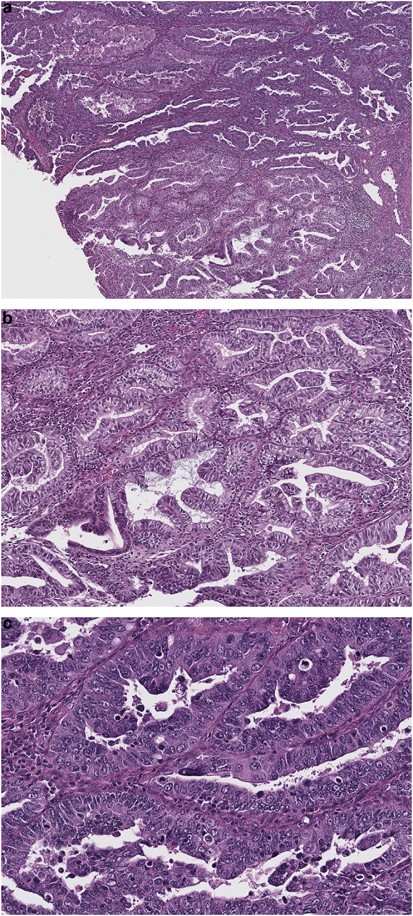

Two recognizably different components were observed in 6 of the 25 cases analyzed. Cases 5, 19, and 24 demonstrated morphological heterogeneity, characterized by foci of endometrioid differentiation, either in the form of glandular areas with smooth luminal borders and low-intermediate nuclear grade (cases 5 and 19) or predominant solid growth pattern with low-intermediate nuclear grade and squamous differentiation (case 24) (Table 2). The endometrioid areas in these three cases were juxtaposed to high-grade components of papillary and glandular architecture, exhibiting irregular luminal borders with tumor cell budding and tufting, and marked nuclear atypia and pleomorphism, morphologically resembling serous carcinoma (Figures 6 and 7). For the purpose of this study, we categorized cases 5, 19, and 24 as mixed endometrioid and serous carcinoma.

(a) Case 5: ‘mixed endometrioid and serous carcinoma’. (b) Endometrioid glandular component with straight luminal borders, secretory change, and low nuclear grade. (c) Glandular architecture with irregular luminal borders, tumor cell budding, and marked nuclear atypia; these features are suggestive of serous carcinoma, but the presence of tall columnar cells also recalls endometrioid differentiation.

Similarly, cases 9, 12, and 13 not only showed confirmatory features of endometrioid adenocarcinoma (at least focally) but also had predominant solid components with marked nuclear atypia and pleomorphism, an ambiguous morphology between endometrioid and solid serous carcinoma. For the purpose of this study, we classified cases 9, 12, and 13 as mixed endometrioid and ambiguous.